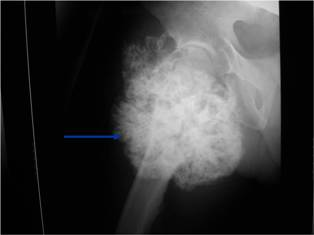

Plain X-ray: Secondary Chondrosarcoma of Proximal Femur